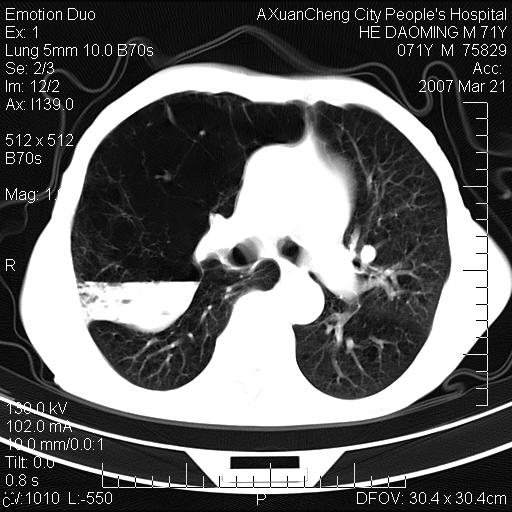

右侧相当于叶间软组织样密度ct值约50hu,请大家讨论是什么性者病变

右下肺大囊肿伴感染.肺气肿,肺大泡.

考虑:慢性支气管炎合并全小型肺气肿、肺大泡、间质纤维化、感染,右斜裂积液。

考虑慢支,肺气肿,肺大泡,间质纤维化;右侧斜裂液气胸考虑(可能因为肺大泡破裂破入斜裂所致).

考虑病变以右上中肺多发肺大泡为主并感染。请结合临床考虑慢支肺气肿,肺心病。

1双肺慢性支气管炎并全小叶型肺气肿肺大泡2间质性纤维化3右侧斜裂积液

考虑:慢性支气管炎合并右侧全小型肺气肿、肺大泡并感染、双肺间质纤维化,右斜裂积液。

如果患者变化一下体位扫描可分辨液平与斜裂的关系。